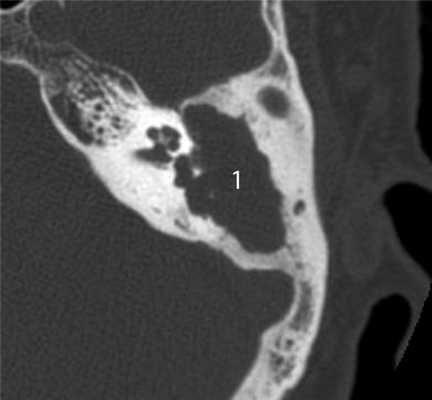

Частым проявлением опухоли височной кости, как было сказано выше, является ее распространение в наружный слуховой проход, что находит свое отражение и на КТ. При небольших размерах полипозного новообразования на КТ в просвете наружного слухового прохода визуализируется образование, исходящее из барабанной полости или проникающее в слуховой проход через его разрушенную стенку (рис. 2). Рисунок 2. Лангергансоклеточный гистиоцитоз. Коронарная проекция правой височной кости. В наружном слуховом проходе определяется полипозное образование (1), на уровне которого верхняя стенка НСП деструктивно изменена. Нарушена пневматизация среднего уха (2). Большой «полип» проявляется на КТ полной обтурацией воздушного просвета слухового прохода мягкотканным образованием (рис. 3). Рисунок 3. Рабдомиосаркома. Аксиальная проекция левой височной кости. Отсутствует пневматизация костного устья слуховой трубы и барабанной полости (1). Просвет наружного слухового прохода обтурирован мягкотканным полипозным образованием (2). Деструкция задней стенки барабанной полости и наружного слухового прохода (3). При анализе данного КТ-признака следует учитывать, что истинные полипы, встречающиеся при хроническом гнойном среднем отите, в отличие от опухолей имеют излюбленную локализацию и чаще всего исходят из верхних отделов барабанной полости.